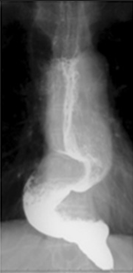

Postoperative barium esophagography. Smooth passage of contrast through the myotomy site (Courtesy Dr. V. Penopoulos)